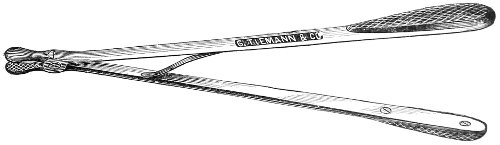

Fig. 4.—Double tenaculum.

The examination of the uterus and other pelvic structures is often facilitated by dragging the uterus downward with a tenaculum while the vaginal or the bimanual examination is being made. Sensation in the cervix is so slight that little or no pain is experienced in this procedure. The anterior or posterior lip of the cervix is caught with the single or the double tenaculum (Fig. 4), guided along the vaginal finger or introduced through the speculum, and the uterus is drawn down by an assistant in case the bimanual examination is being made, or by the external hand of the examiner in case a simple vaginal examination is made. When this is done the utero-sacral ligaments are made tense, and can be felt like two cords extending from the sides of the cervix outward and backward to the pelvic wall. The posterior surface of the uterus can be palpated often as high up as the fundus. The method is especially useful when the examination is made by the rectum, and in this way the whole posterior surface and the fundus of the uterus may be palpated (Fig. 5).

Fig. 5.—Bimanual examination with one finger in the rectum. The uterus is drawn down with the double tenaculum.